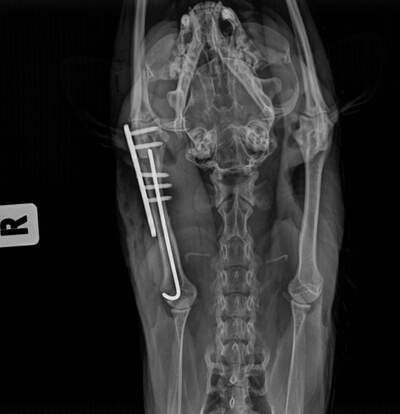

Сейчас она у меня дома в переписке. Похоже, вывихнута лапа, сильный стресс. Пока ничего не пьет, не ест.

Завтра поедем в ветеренарку....